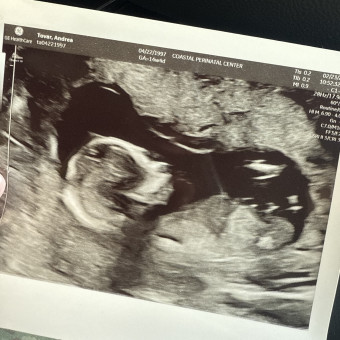

Andrea's Baby Registry

Andrea Denise Tovar

August 20, 2026